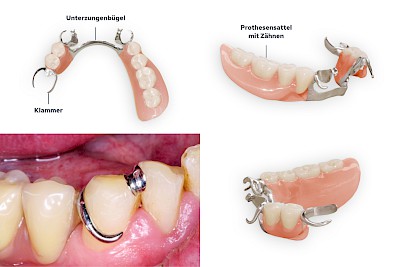

Teilprothese

Teilprothesen sind eine Möglichkeit, Zahnlücken mit einer herausnehmbaren Prothese zu ersetzen.

Bestandteile

- Zähne (meist aus Kunststoff) auf rosafarbenen Kunststoff-Sätteln, die den zahnlosen Kieferabschnitten aufliegen

- Verbindungselemente für den Halt und zur Verankerung der Prothesen an den Restzähnen

- Sogenannte große Verbinder (Unterzungenbügel oder Gaumenbügel) zur Stabilisierung der Prothese insgesamt und zur Reduzierung der Gefahr, die Prothese zu verschlucken bzw. zu aspirieren

Unterscheidung nach Verbindungs- oder Verankerungselement

- Klammerprothesen

- Geschiebeprothesen

- Teleskopprothesen (Doppelkronen)

Manchmal sind Zahnprothesen auch über komplizierte Verankerungselemente (Riegel) mit den Restzähnen verbunden. Zudem werden nicht selten die verschiedenen Verbindungselemente kombiniert. Teilprothesen sind sehr vielfältig und zum Teil technisch sehr aufwendig gefertigt. Deshalb ist auch die Handhabung (Einsetzen, Herausnehmen, Reinigen) nicht immer einfach und selbsterklärend. Wenn immer möglich, sollte der betroffene Mensch selbst seine Prothesen entnehmen und einsetzen – meist haben diese jahrelange Übung und kennen die "Tricks"

Verbindungselemente 5 Bilder

Vor allem bei Klammerprothesen muss darauf geachtet werden, dass die Wangen und Lippen gerade beim Einsetzen nicht verletzt oder eingeklemmt werden. Nach dem Einsetzen sollte überprüft werden, ob die Wangen und Lippen "frei" sind.